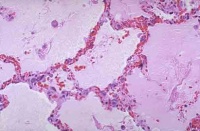

肺表面苍白,含水量增多,切面有大量液体渗出显微镜下观察,可将其分为间质期,肺泡壁期和肺泡期。

间质期是肺水肿的最早表现,液体局限在肺泡外血管和传导气道周围的疏松结缔组织中,支气管、血管周围腔隙和叶间隔增宽,淋巴管扩张。液体进一步潴留时,进入肺泡壁期。液体蓄积在厚的肺泡毛细血管膜一侧,肺泡壁进行性增厚。发展到肺泡期时,可见充满液体的肺泡壁丧失了环形结构,出现褶皱。无论是微血管内压力增高还是通透性增加引起的肺水肿,肺泡腔内液体的蛋白均与肺间质内相同,提示表面活性物质破坏,而且上皮丧失了滤网能力。